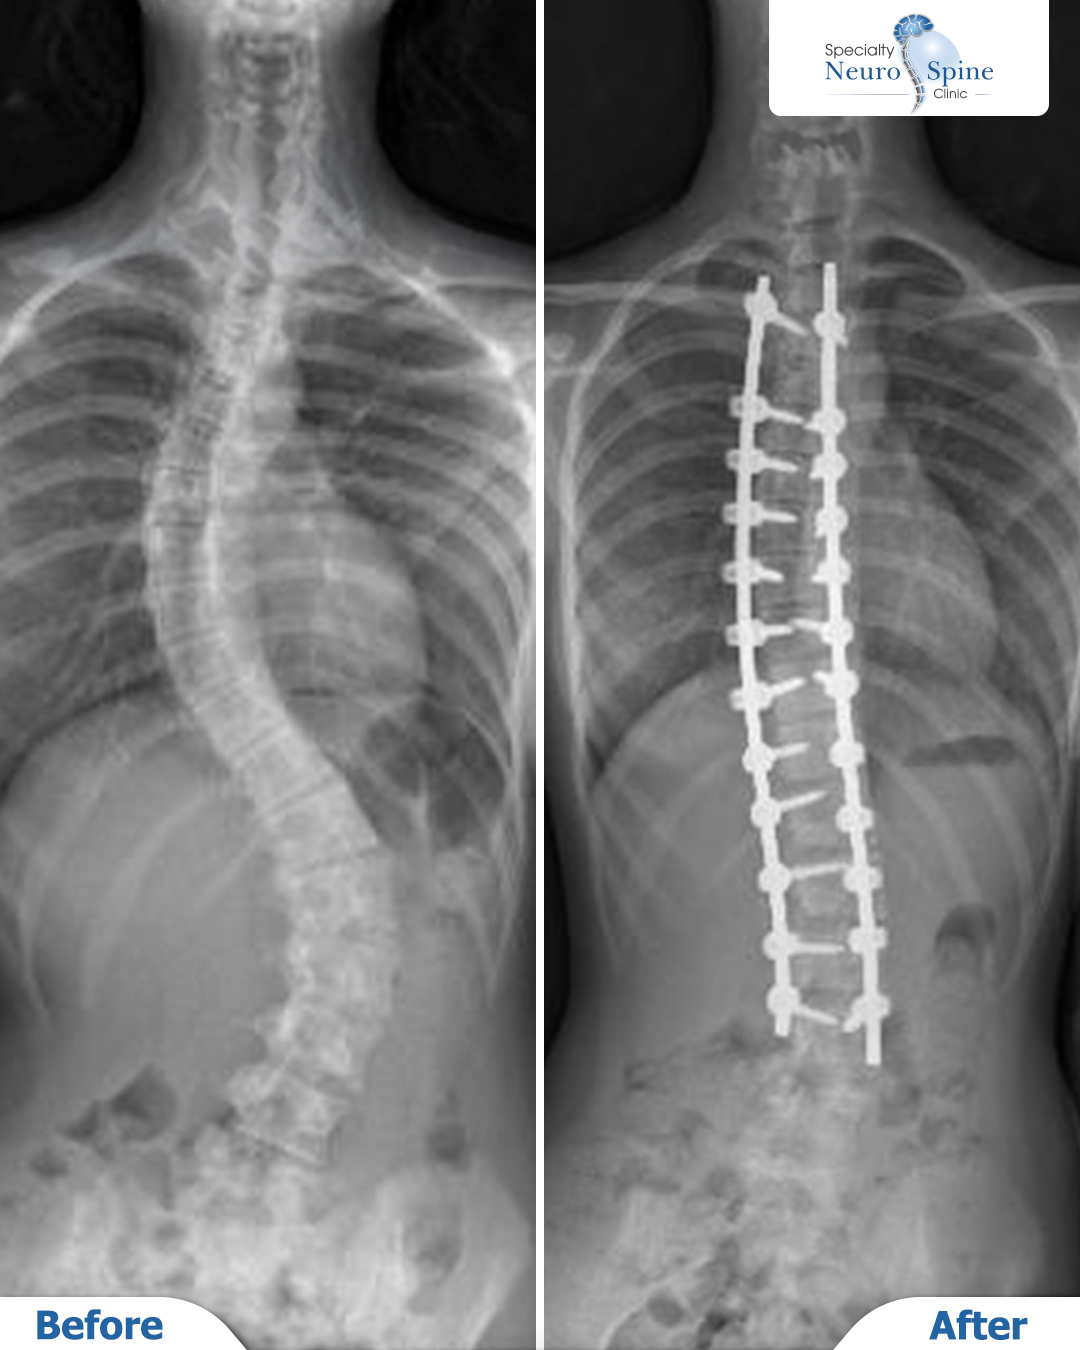

The X-ray images of our patient, Aysha (13 years old from Pakistan), illustrate the results following a spinal deformity correction surgery extending from the T3 to L4 vertebrae.

The images demonstrate a clear transformation between the pre-operative and post-operative stages, highlighting a remarkable restoration of spinal alignment and optimal vertebral stability.